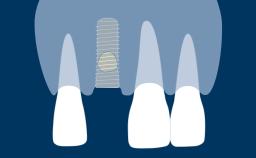

- intraoperative complications of lateral window sinus floor elevation

- intraoperative complications of transcrestal sinus floor elevation